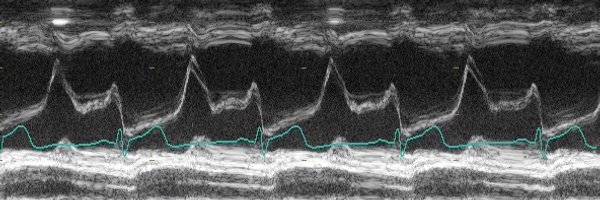

OK seriously this might be the spookiest Echo I’ve ever seen 👻 What’s the diagnosis?